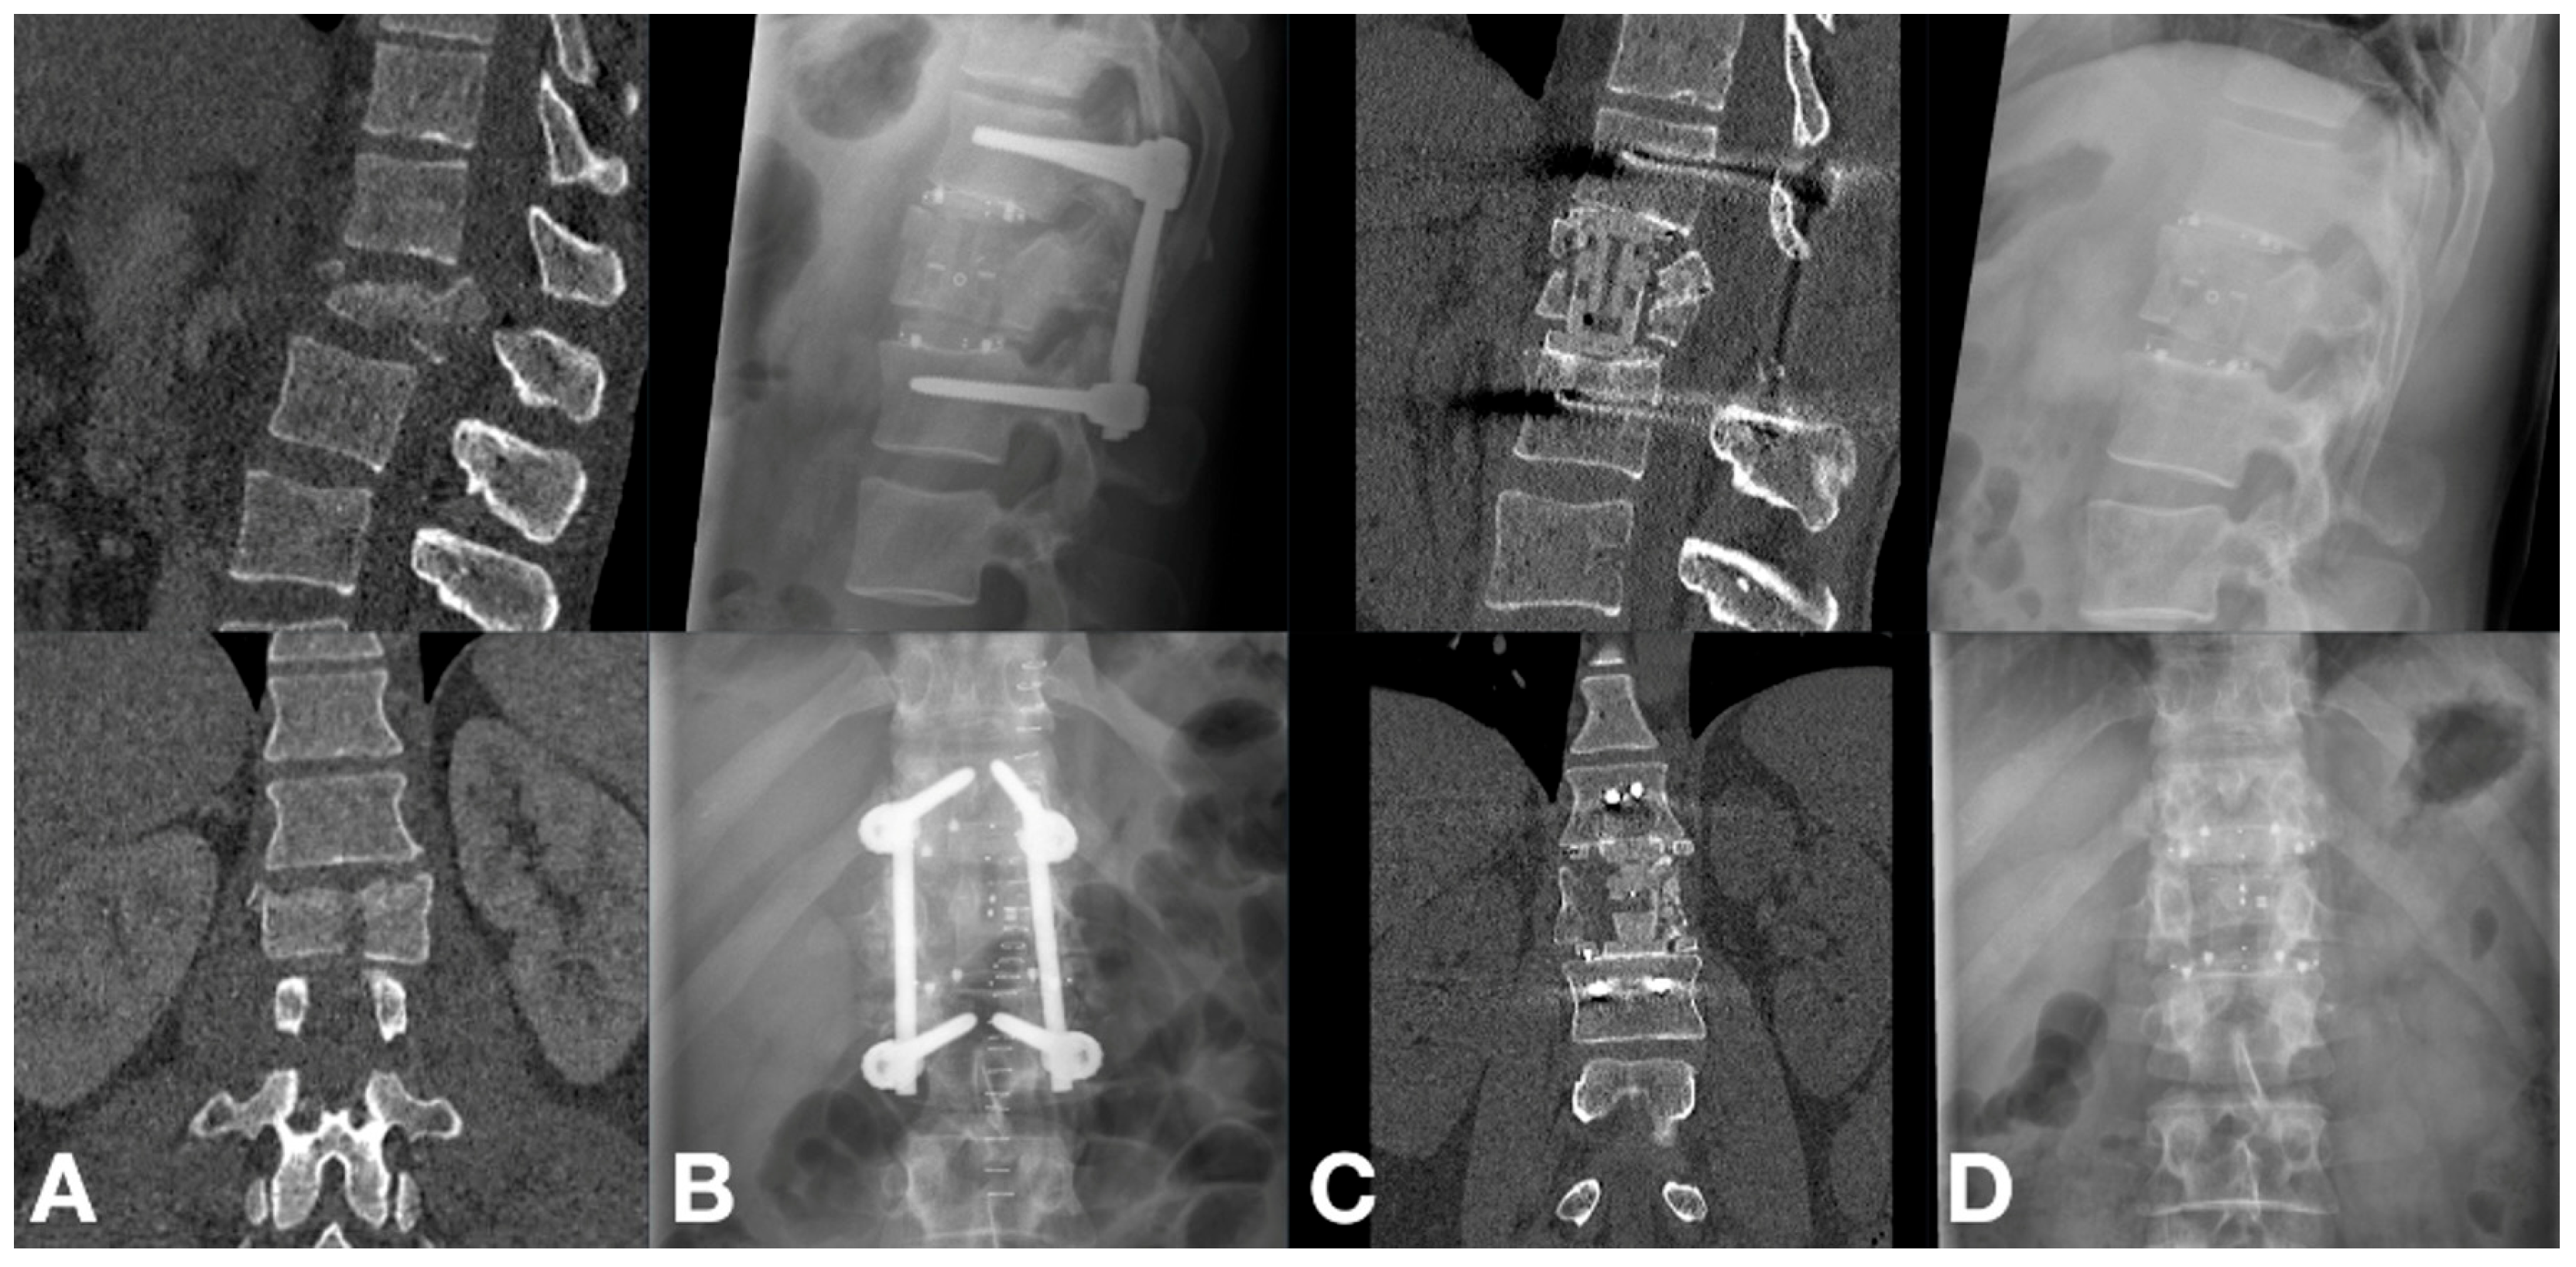

3.2. Radiographic Outcomes

3.3. Clinical Outcomes